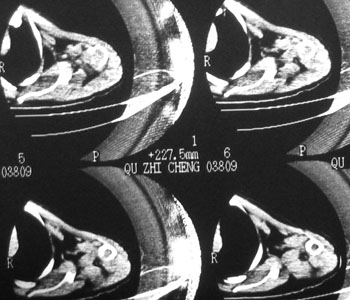

性别 男  62岁 因咳嗽及左肱骨剧烈痛疼数天来院检查。

考虑右肺中叶肺癌并左肱骨转移伴病理性骨折。

支持右肺中心型肺癌并肺内及左肱骨转移伴病理性骨折

右侧中心型肺癌并左侧肱骨骨转移病理性骨折存在

右肺中心型肺癌并中叶不张,左肱骨溶骨性转移并病理骨折。